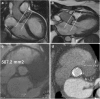

Transcatheter Aortic Valve Implantation (TAVI) is increasingly being used in patients with severe aortic stenosis who are not candidates for surgery. ECG-gated CT angiography (CTA) plays an important role in the preoperative planning for these devices. As the number of patients undergoing these procedures increases, a subset of patients is being recognized who have contraindications to iodinated contrast medium, either due to a prior severe allergic type reaction or poor renal function. Another subgroup of patients with low flow and low gradient aortic stenosis is being recognized that are usually assessed for severity of aortic stenosis by stress echocardiography. There are contraindications to stress echocardiography and some of these patients may not be able to undergo this test. Non-contrast MRI can be a useful emerging modality for evaluating these patients. In this article, we discuss the emerging indications of non-contrast MRI in preoperative assessment for TAVI and describe the commonly used MRI sequences. A comparison of the most important measurements obtained for TAVI assessment on CTA and MRI from same subjects is included. Teaching Points • MRI can be used for preoperative assessment of aortic annulus. • MRI is an alternate to CTA when iodinated contrast is contraindicated. • Measurements obtained by non-contrast MRI are similar to contrast enhanced CTA. • MRI can be used to assess severity of aortic stenosis.